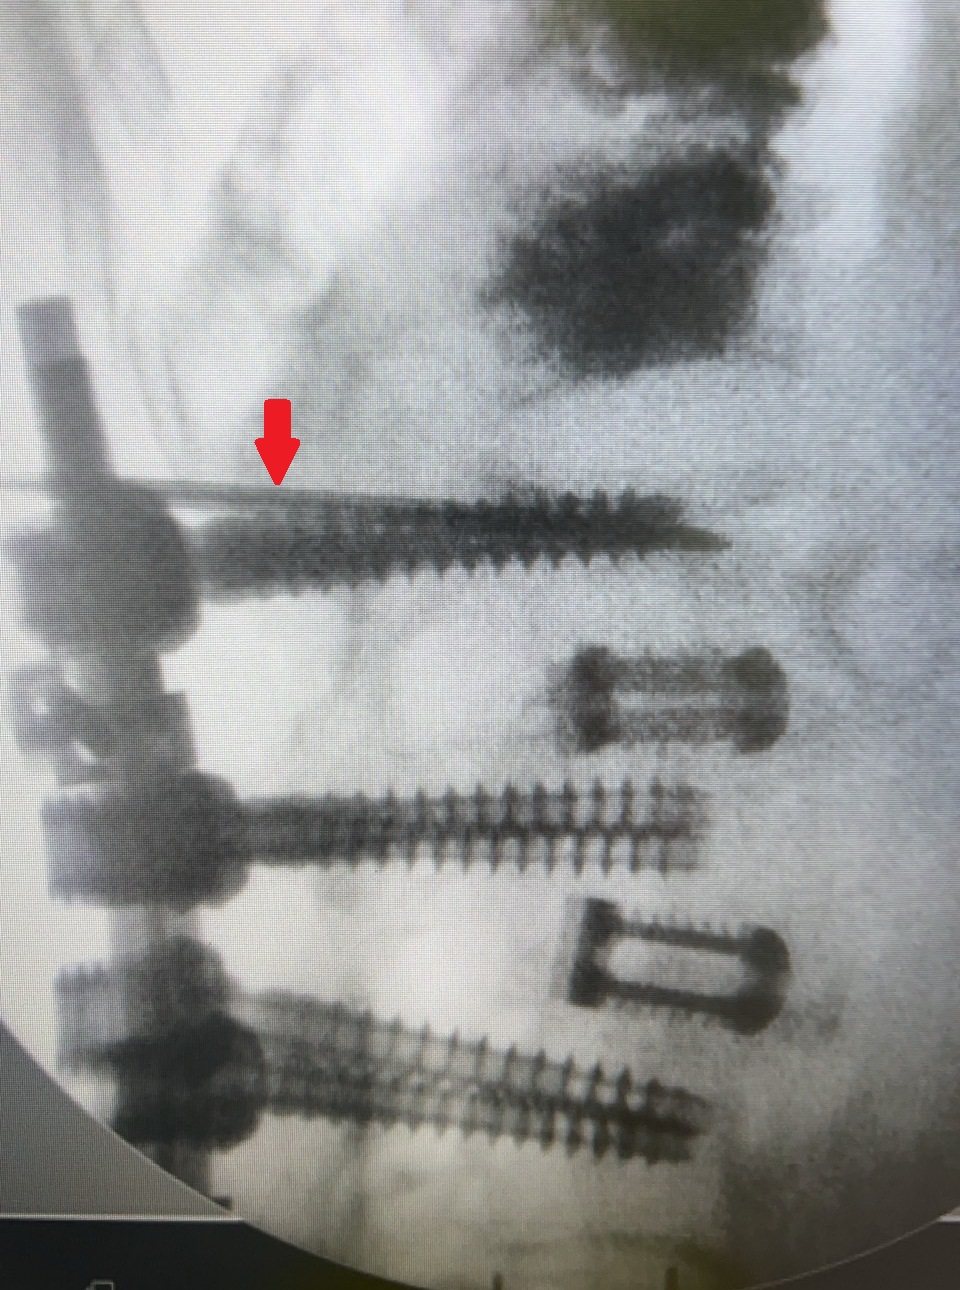

容志雄醫師分享近日治療的兩個案例,一是高齡93歲的奶奶,過去脊椎第3、4、5節曾手術打鋼釘,此次受傷剛好是在第3節上緣,評估病人因個子較高,加上第一支鋼釘打入的位置較往下一些,因此利用上緣狹小的空間,順利完成灌骨泥治療。第二位病人是82歲的奶奶,個子嬌小且鋼釘位置打得很好,能打入骨泥的空間更小,所幸在使用孩童專用的細小鋼針後,也成功灌入骨泥,解決壓迫性骨折的疼痛。兩位病人的困難度都相當高,所幸在手術過程中透過C型臂X光機準確的定位,及醫師專業的判斷,才能在非常狹窄的空間下,精準地將骨泥灌入受傷位置。

82歲奶奶因手術空間狹小,在X光機導引下,以細小鋼針(箭頭處)順利完成手術。